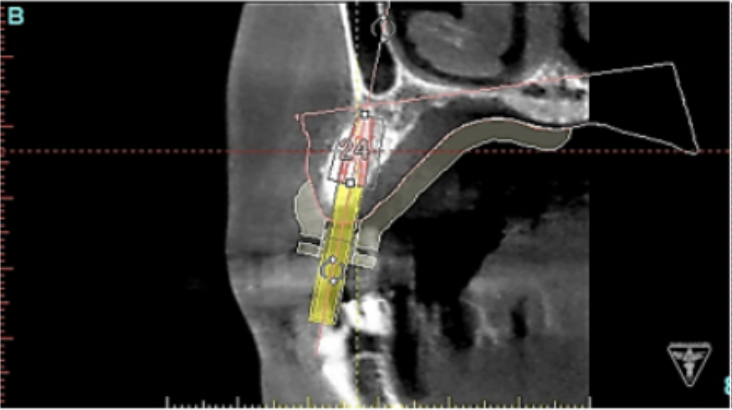

サージカルガイドの作成

インプラント埋入前のCTによる確認